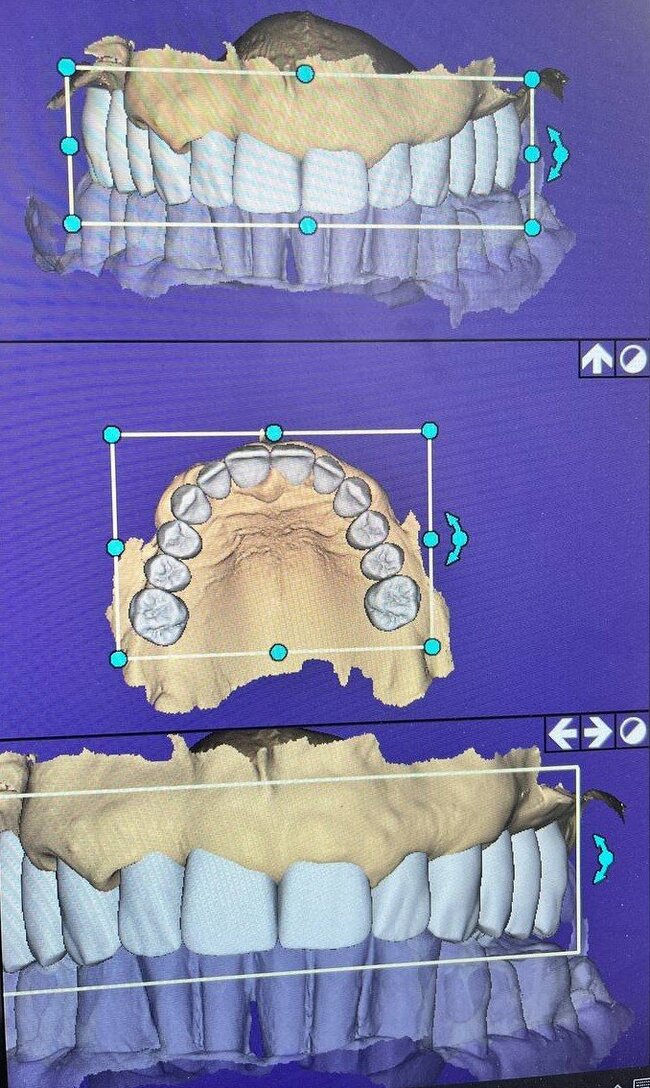

Примерка временного протеза "всё на 4-х"

Постановка на воске.

Временный протез "всё на 4-х", постановка на воске

А теперь посмотрим на картину с антагонистами.

Важно - мы не переделывали прикус! А повторили тот, что у пациента уже был, только высоту вернули.

Проверяем попадание в прикус.

Помещаем протез в полость рта, "прикручиваем" к имплантатам. Очень хорошо попали с первого же раза в комфортное положение.